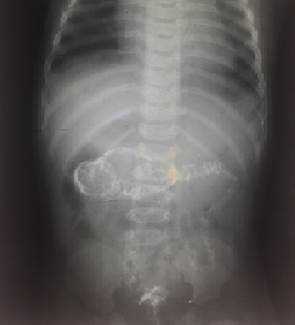

На рисунках 4 и 5 представлена картина кишечной инвагинации при рентгенологическом исследовании.

Рис. 5. Ирригограмма после опорожнения толстой кишки - симптом «кокарды»

Обзорная рентгенография показала небольшое количество газа в правой нижней части живота и признаки кишечной непроходимости: расширенные петли кишечника с чередованием тёмных и светлых участков, указывающих на наличие жидкости.

При повторном прощупывании живота инвагинат больше не определялся, а рентгеновский снимок показал равномерное распределение расширенных петель кишечника без жидкости и газа. В брюшной полости свободного газа также не было.